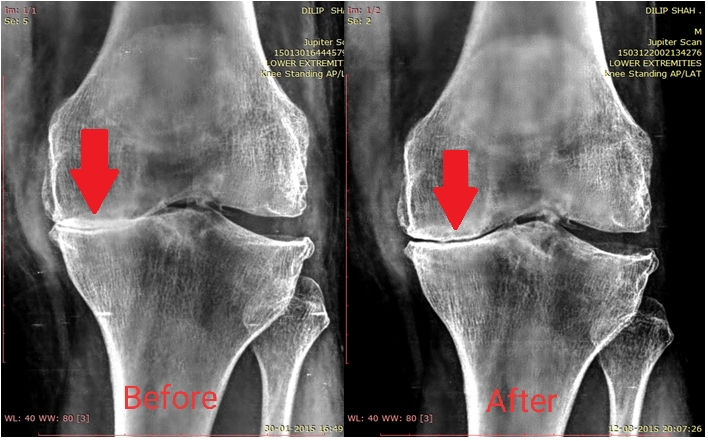

Chronic Osteoarthritis of the Knee is all about Improving Joint Space width. In a first of its kind study in the world, we have proven that it is possible to reverse JOINT SPACE WIDTH (JSW) between the Femur (thigh bone) and Tibia (Leg bone) in order to improve complications and symptoms of Osteoarthritis Knee. Traditionally, all Treatment give to an Osteoarthritic knee is focussed on Symptomatic relief of Pain/Swelling, while Scientific studies have focused only on regrowing Cartilage at the knee. We give you Images of patient's X-rays (with permission) to show you that Knee Osteoarthritis is fixable without Surgery.

Similar images from Osteoarthritis Knee Study

Other Images of improved Medial Joint Space width at the Knee in a Male patient, in the "Reversal of Osteoarthritis Study" at our Clinic facility

Eg.: Osteoarthritis is a degenerative condition for which Medical texts say that there is no cure. But through Clinical research studies, we have shown that Osteoarthritic changes in the Knee (like Joint Space Width and Osteophytes) can be reversed through aggressive Physiotherapy treatment. Such patients, once discharged from our care are scheduled once a month (or once in 6 weeks) to ensure that the patient is compliant with the exercise program and there is no reversal of Osteoarthritic changes. See X-rays below.

In the above images - one can see the Patellar Joint Space Width change in an Osteoarthritic knee, after Physiotherapy treatment. What you may find interesting is, that these images were taken in unilateral standing (standing on one leg). The Joint Space Width did not collapse despite standing on one leg.